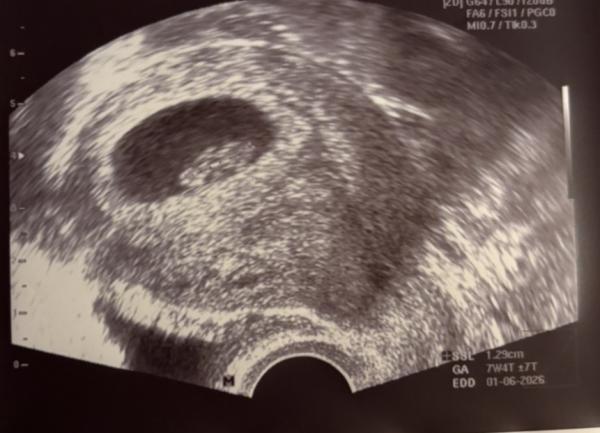

Hey kennt sich jemand mit NUB oder Ramzi aus? Es ist mein 2. Kind und ich wusste bei dem ersten oh das wird ein Junge, habe mich von meinem Mann überzeugen lassen es wird ein Mädchen tatdaaaa es wurde ein Junge & Als ich den Test gemacht habe und den 2. Strich gesehen habe dachte ich direkt ohhhh ich kann Kleidchen kaufen jetzt meine Frage was denkt ihr welches Geschlecht es ist? 1. Bild SSW 7+4 2. + 3. Bild SSW 10+5

Bild zu NUB oder Ramzi - Forum für Juni - Mamis

Herzlichen Glückwunsch zur erneuten Schwangerschaft!    Die Ramzi-Methode ist natürlich nicht zu 100% wahr, aber ich würde auf einen Jungen tippen. Sobald du das Geschlecht weißt, kannst du ja gerne mal eine Rückmeldung geben.    Bis dahin alles Gute euch und genieße die Kugelzeit.🤗

Tatsächlich würde ich laut ramzi wenn vaginal Untersuchung auch auf Jungen tippen 🥰